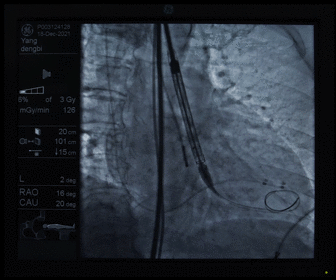

胶囊腔定位

瓣膜释放

经分析研判,拟从右侧股动脉穿刺入路,使用20mm球囊预扩,采取downsize手术策略,选用L23号的VenusA-Valve瓣膜,因患者为横位心,瓣膜释放同轴性差,容易发生移位,故采用VenusA-Plus可回收输送系统确保瓣膜的稳定释放,瓣膜释放后结合造影和超声情况,决定是否后扩。